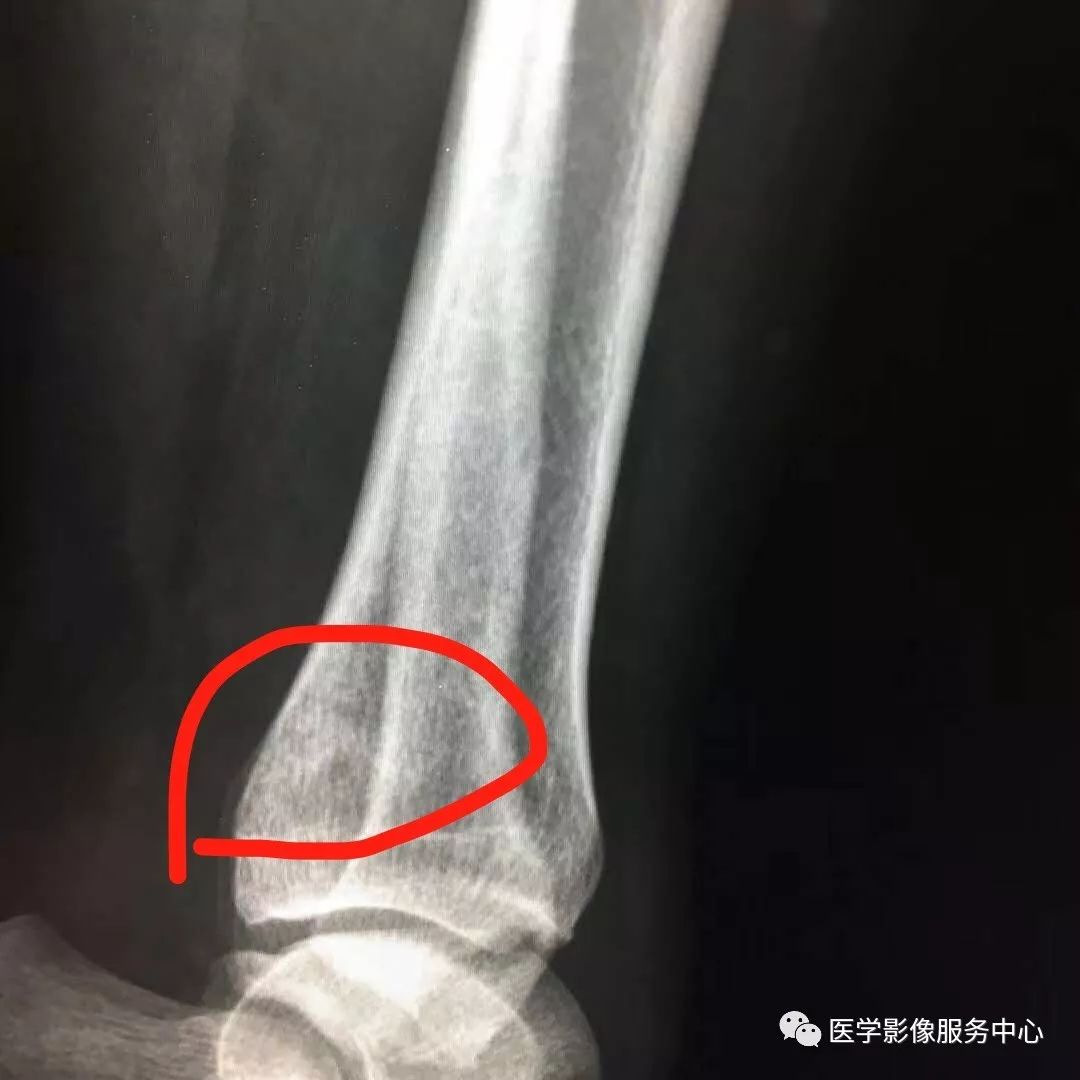

Pilon骨折常常伴随极度粉碎的骨折和严重的软组织损伤,选择合适的手术入路就成了手术的关键。